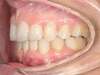

Cas 3 : Description

Encombrement aux deux arcades.Traitement par gouttières.

Avant

Après